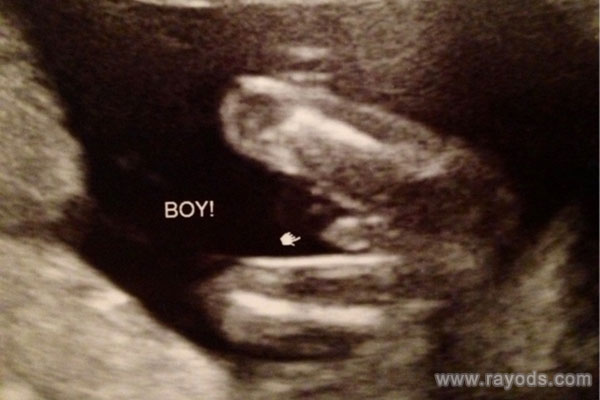

(男宝腿部间性别特征)

当然,产检能够看到胎儿宝宝的发育情况,不少人都觉得自然能够看到胎儿宝宝的性别特征。孕周太小看的不清晰,一般到了20周以后,男胎也好女胎也好生殖器发育已经显现,随着月份的增大,医生会清晰看到胎儿的各个部位发育,其中自然也包括生殖器。那么30周b超男女腿部间的区别是如何的呢?本文有图有真相来给大家揭秘一下。

按照胎儿正常的发育来看,生殖器发育一般会在18-20周正式开始发育,特别是男孩的小,一般要等到18周左右才会正式下来,而女孩的话这个时候双腿间还是平平的。根据b超技术来看,24周做四维彩超的时候是可以清晰明确看到男孩女孩的生殖器的,30周胎儿外生殖器官发育成熟,生殖系统还未完善,此时男女腿部间的区别很好区分。

如果是男孩会看到凸起的一坨,有的还会看到上面的小尖尖,女孩则是圆圆的一坨,有点鼓包样。30周的时候男孩女孩胎儿的生殖器已经很好区分了,一般的分辨依据就是根据其外生殖器结构,男孩的要更明显得多。在30周之前男孩生殖器这里一般会有圆球或者亮点,女孩胎儿在30周的时候看双腿间的话会有白线,一般都是三条白线,代表的是女孩的大小***。

但四维彩超的主要目的并非是看胎儿性别,当然医生也不会明说,这是违法的。在网上有不少已生宝妈透露自己在24-30周b超的时候很幸运的看到了胎儿宝宝的生殖器,据他们的介绍来看,和上文中的说法基本一致。不少已生宝妈都表示男孩胎儿发育要比女孩快一些,生殖器发育虽然维持的是一整个孕周,但30周时性别器官已经非常明显了。

因此,如果大家有幸看到胎儿腿部间有凸出的,就像是小乌龟一样的,那十有八九怀的是男孩,反之如果腿部间平平的甚至还会看到三条白线的话一般就是女孩了。当然,提醒一下各位妈妈们,这个时候胎儿胎动活跃,角度和体位也会随时变换,有时候很容易将手指或者脐带弄混淆,这个时候就要看生殖器的反光和亮点来区分了。